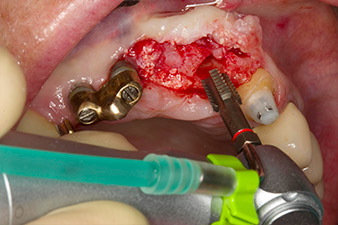

Gewindeschnitt mit dem Winkelstück WS-75 L

Abb. 3: Gewindeschnitt mit dem Winkelstück WS-75 L bei einer Übersetzung von 20:1 (Programm P4). Hilfreich sind hier das hohe Drehmoment des Implantmed, das Hexagon-Spannsystem für sichere Kraftübertragung und die automatische Umkehr der Drehrichtung bei zu hohem Widerstand.

Der Alveolarknochen erweist sich an Position 22 als ausreichend dimensioniert. Die Abbildungen 2 und 4 zeigen die Implantatbett-Aufbereitung, den Gewindeschnitt und die Implantation mit dem Implantmed.